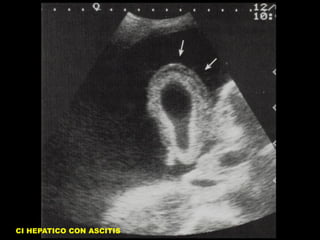

CI HEPATICO CON ASCITIS

INSUFIECIENCIA HEPATICA

HEPATITIS AGUDA FULMINANTE